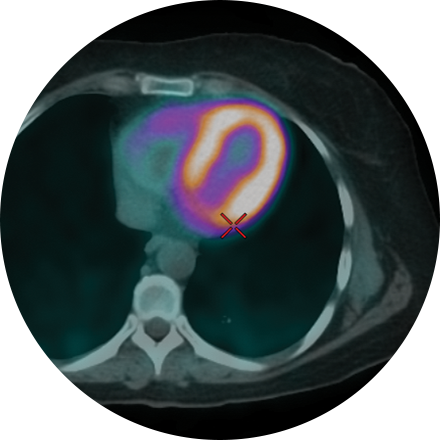

Myocardial Perfusion

This non-invasive exam shows how well blood perfuses (flows through) your heart muscle—in other words, how well your heart is pumping. Sometimes known as a nuclear stress test, it can be performed while the patient exercises on a treadmill or, if that is inadvisable, using a medicine that simulates the effect of exercise on the heart. Myocardial perfusion is an effective way to assess narrowed arteries, the effects of a past heart attack, or the viability of further procedures, such as a stent.